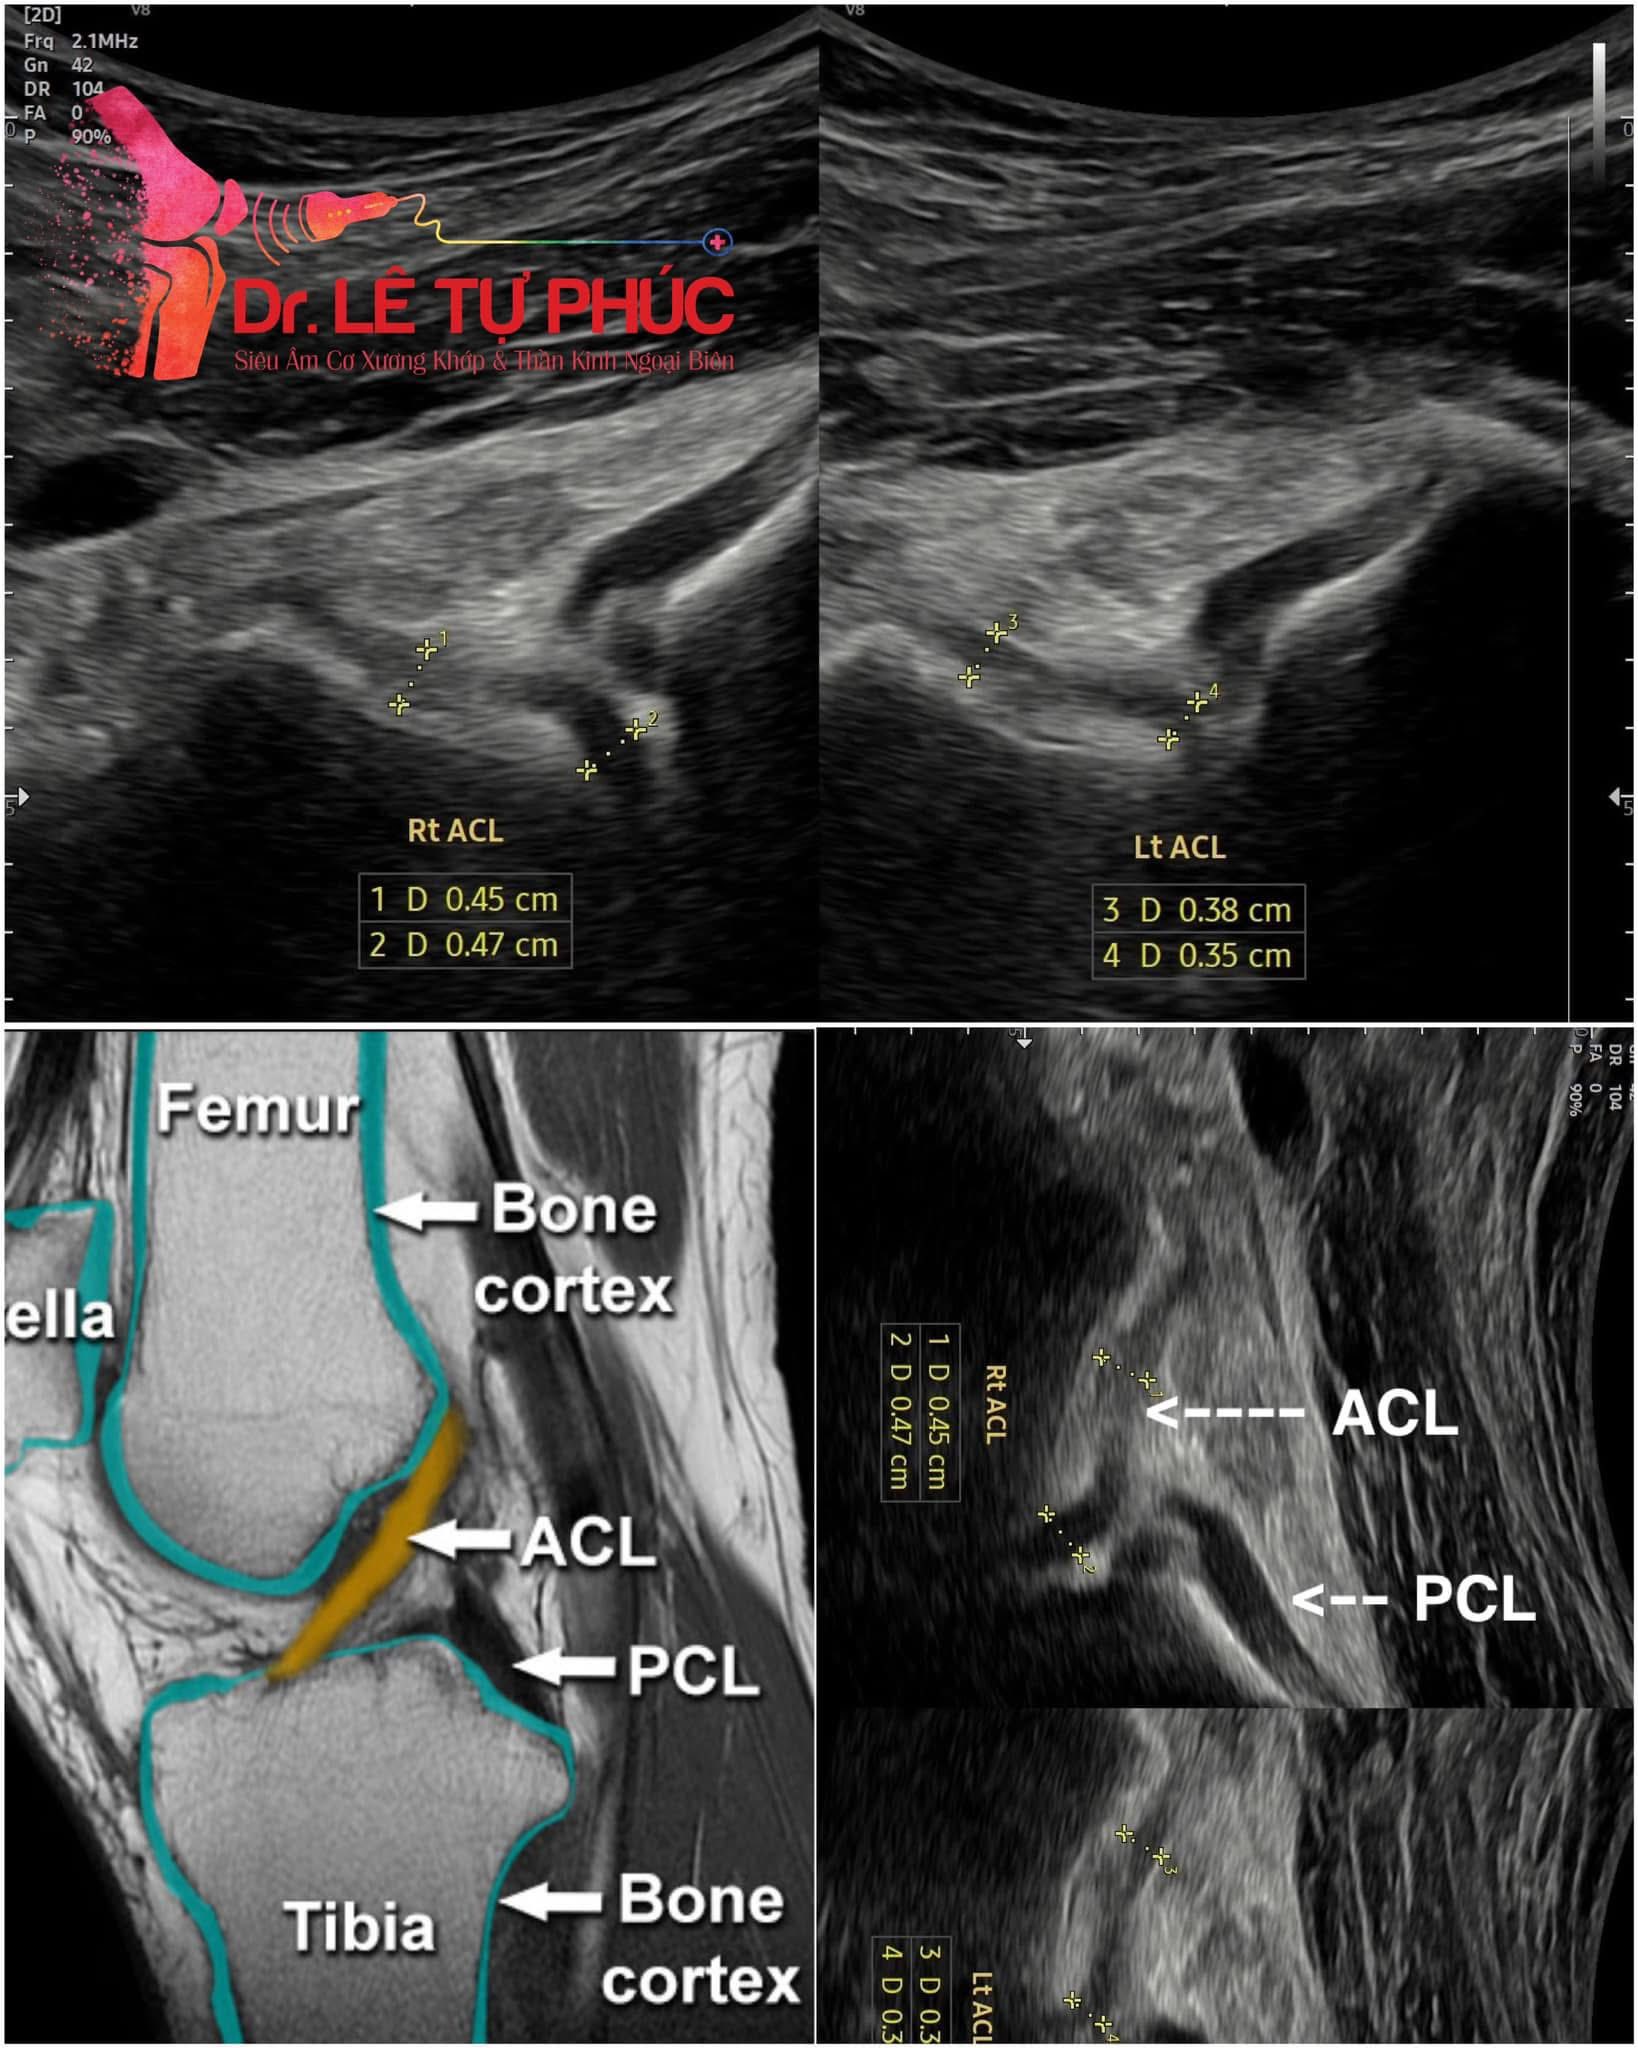

Chấn thương thể thao là một trong những lĩnh vực đặc biệt mà máy siêu âm cơ xương khớp thể hiện hiệu quả vượt trội. Trong các hoạt động thể thao, các vận động viên thường gặp các tổn thương như rách dây chằng, đứt gân, bong gân, viêm gân, phù nề cơ hay tràn dịch khớp. Với khả năng cận cảnh các cấu trúc mềm, siêu âm giúp bác sĩ xác định chính xác vị trí, mức độ tổn thương qua đó đưa ra phương pháp điều trị phù hợp.

Một trong những ưu điểm lớn nhất của máy siêu âm cơ xương khớp chính là khả năng cung cấp hình ảnh thời gian thực, giúp bác sĩ quan sát trực tiếp và đánh giá chính xác cấu trúc bị tổn thương. Hơn nữa, thiết bị còn có thể tùy chỉnh phù hợp để khảo sát các vị trí khác nhau của cơ thể, từ đó phát hiện các tổn thương nhỏ nhất mà các phương pháp khác khó phát hiện. Trong thực tiễn, máy siêu âm cơ xương khớp được ứng dụng rộng rãi trong chẩn đoán các bệnh lý như viêm khớp, gai khớp, thoái hóa khớp, tổn thương dây chằng, gân, rách cơ, hay xác định các chấn thương thể thao. Công nghệ này còn giúp theo dõi quá trình hồi phục của bệnh nhân sau phẫu thuật hoặc các phương pháp điều trị bảo tồn khác. Nhờ đó, quá trình điều trị trở nên chính xác, nhanh chóng và hạn chế tối đa các rủi ro.